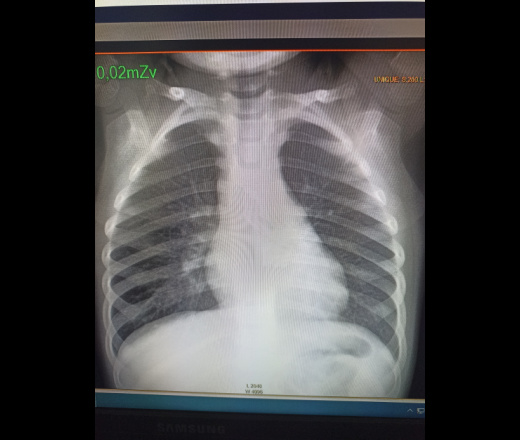

Дано ребенок 1 год 7 месяцев. Болеет уже 3 дня. Силтный кашель, плохосбиваемая температура до 39.3, за день может подниматься 6 раз. Сильный кашель, изначально с мокротой, плачет.

Качество изображение очень скверное. Грубой патологии не видно

С учётом клинических данных ( лихорадка 39 градусов, в течении 3-х суток) , боковая проекция не будет лишей ( в принципе , стандарт  исследование лёгких в 2-х проециях). Посоветовал бы коллегам проводить редактирование изображений после выполнения снимка ( большая оптическая плотность изображения, которая , редактируется яркостью и контрастностью изображения).